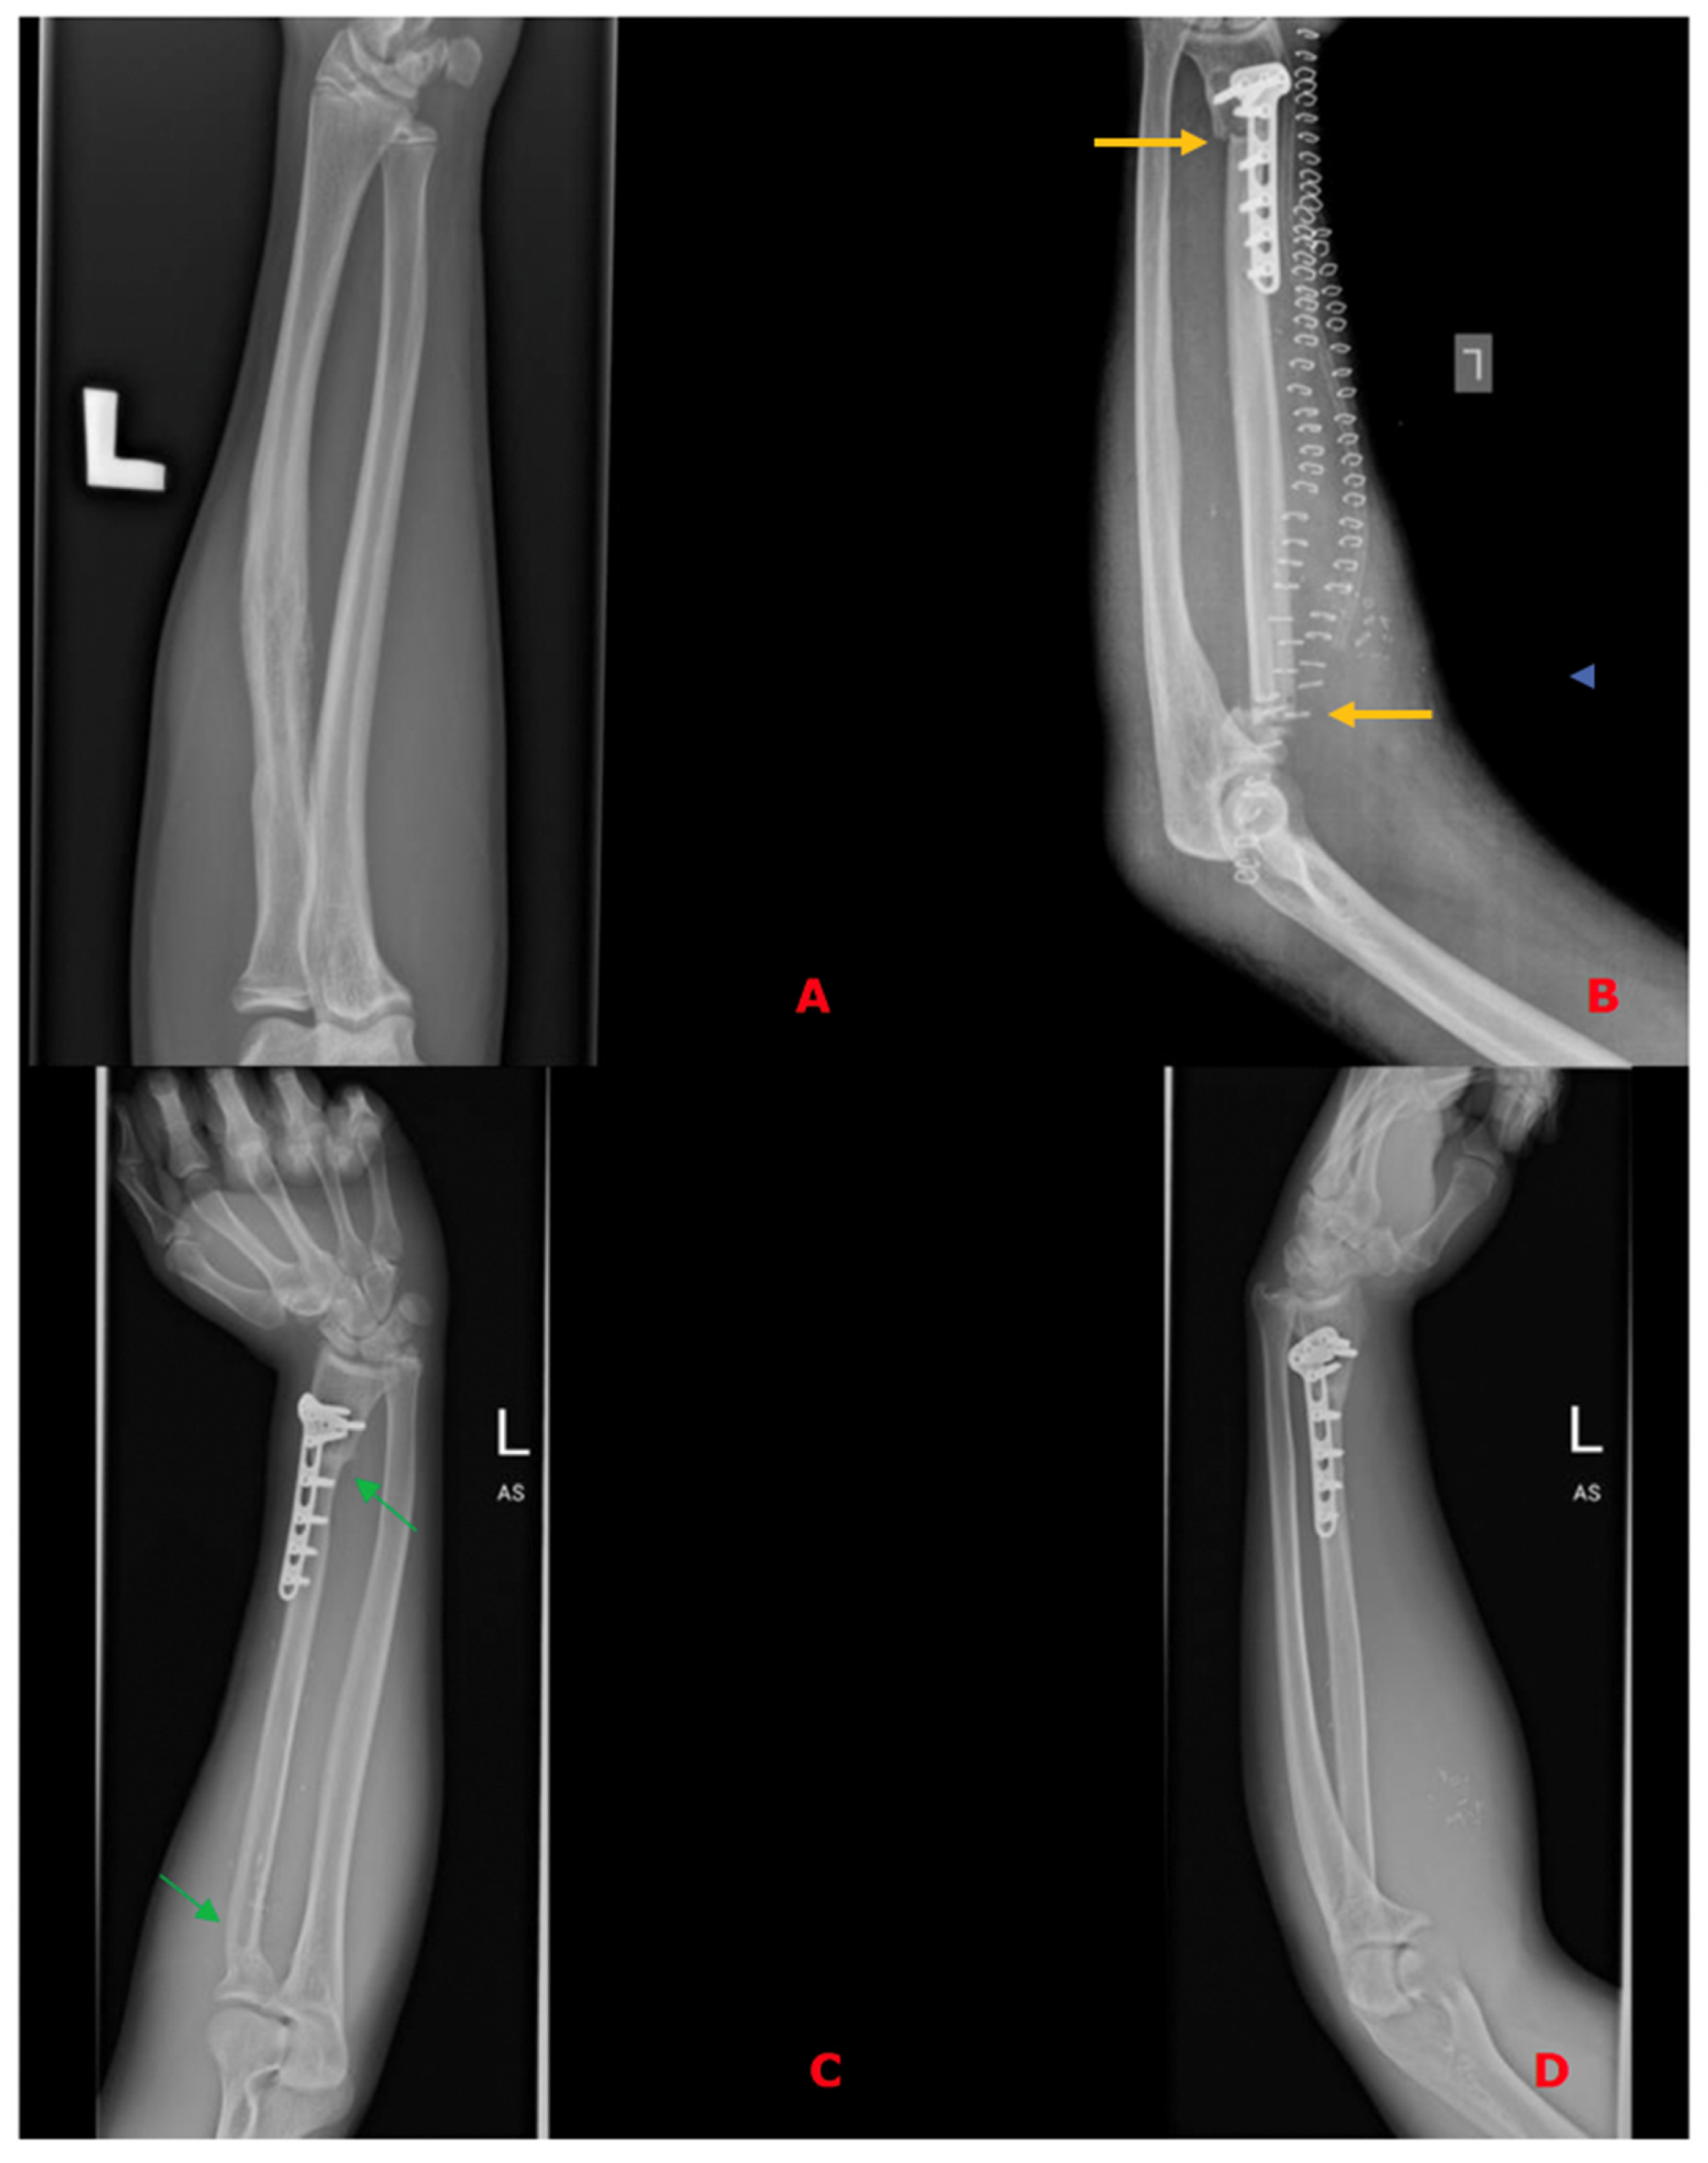

In all of the patients included, a fibula free flap (FFF) was applied to carry out the reconstruction with possible modifications regarding the harvest of the flap when the metaphysis was involved. The intraoperative photographs of the FFF harvest are presented in Figure 2. Most commonly, a FFF was applied to reconstruct the diaphyseal part of the long bone. In cases of the short stump of the long bone after resection part, to prevent arthrodesis, due to the lack of technical possibility of stabilizing the proximal part of the radius using a titanium plate, stabilization with non-dissolvable sutures was used by drilling holes within the proximal part of the fibula, with subsequent thread insertion through the holes created and suture fixation through the cortical layer of the remaining proximal stump of the radius (Figure 3). When the resection was not limited only to the shaft of the long bone but also included partially the proximal metaphysis of the radius, the FFF was harvested with the head of the fibula in a typical manner. During the harvest of the fibular head, the deep peroneal nerve was carefully dissected off the bone and spared, which is the crucial point for mitigating donor-site morbidity. The fibular head replaced the function of the head of the radius at the humero-radial joint and was inserted directly into the spared annular ligament of the radius, maintaining the functionality/mobility of the limb and avoiding the endoprosthesis of the humeroradial joint at the same time (Figure 4). This solution was possible due to the sparing of the annular ligament, which ensured adequate stabilization of the fibular head.

When the tumor infiltrates the metaphysis of the long bone, which requires resection of this part of the bone—most commonly to treat this area and preserve functionality of the joint—the endoprostheses are applied, and of course, in many cases, it is an unavoidable solution. Nevertheless, in the case of metaphyseal involvement in this study group, to avoid the implementation of artificial material, mitigating the risk of complications specific for endoprostheses and avoiding arthrodesis at the same time, we decided to harvest the fibula free flap with its head to maintain the mobility of the humeroradial joint. The head of the fibula was inserted directly into the spared annular ligament of the radius (Figure 4, marked with a green arrow).

Figure 4. (A)—preoperative X-ray of the left upper limb with diagnosed Ewing Sarcoma of the radius; (B)—fibula free flap harvested with the fibular head (green arrow) placed within the wound bed after resection of the radial bone; (C)—intraoperative X-ray presenting the proper position of the fibular head within the annular ligament; and (D)—postoperative X-ray of the upper limb with a visible skin island of the fibula free flap (as a monitor of the appropriate perfusion of the buried part of the flap).